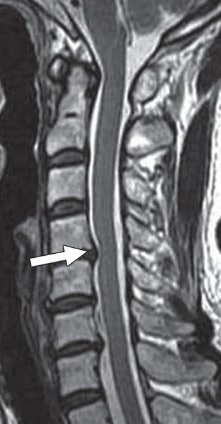

| Image of a 61-year-old woman with cervical canal stenosis. Sagittal T2-weighted fast spin-echo image shows grade 2 stenosis at C4-5 level (arrow). Spinal cord is compressed and deformed but shows no signal changes. Grade 1 stenoses were also seen at C5-6 and C6-7 levels. Image courtesy of AJR. |

Kang and colleagues used T2-weighted sagittal MR images to classify cervical canal stenosis into four grades. Grade 0 meant there was no canal stenosis, grade 1 signified subarachnoid space obliteration exceeding 50%, grade 2 indicated spinal cord deformity, and grade 3 indicated spinal cord signal change.